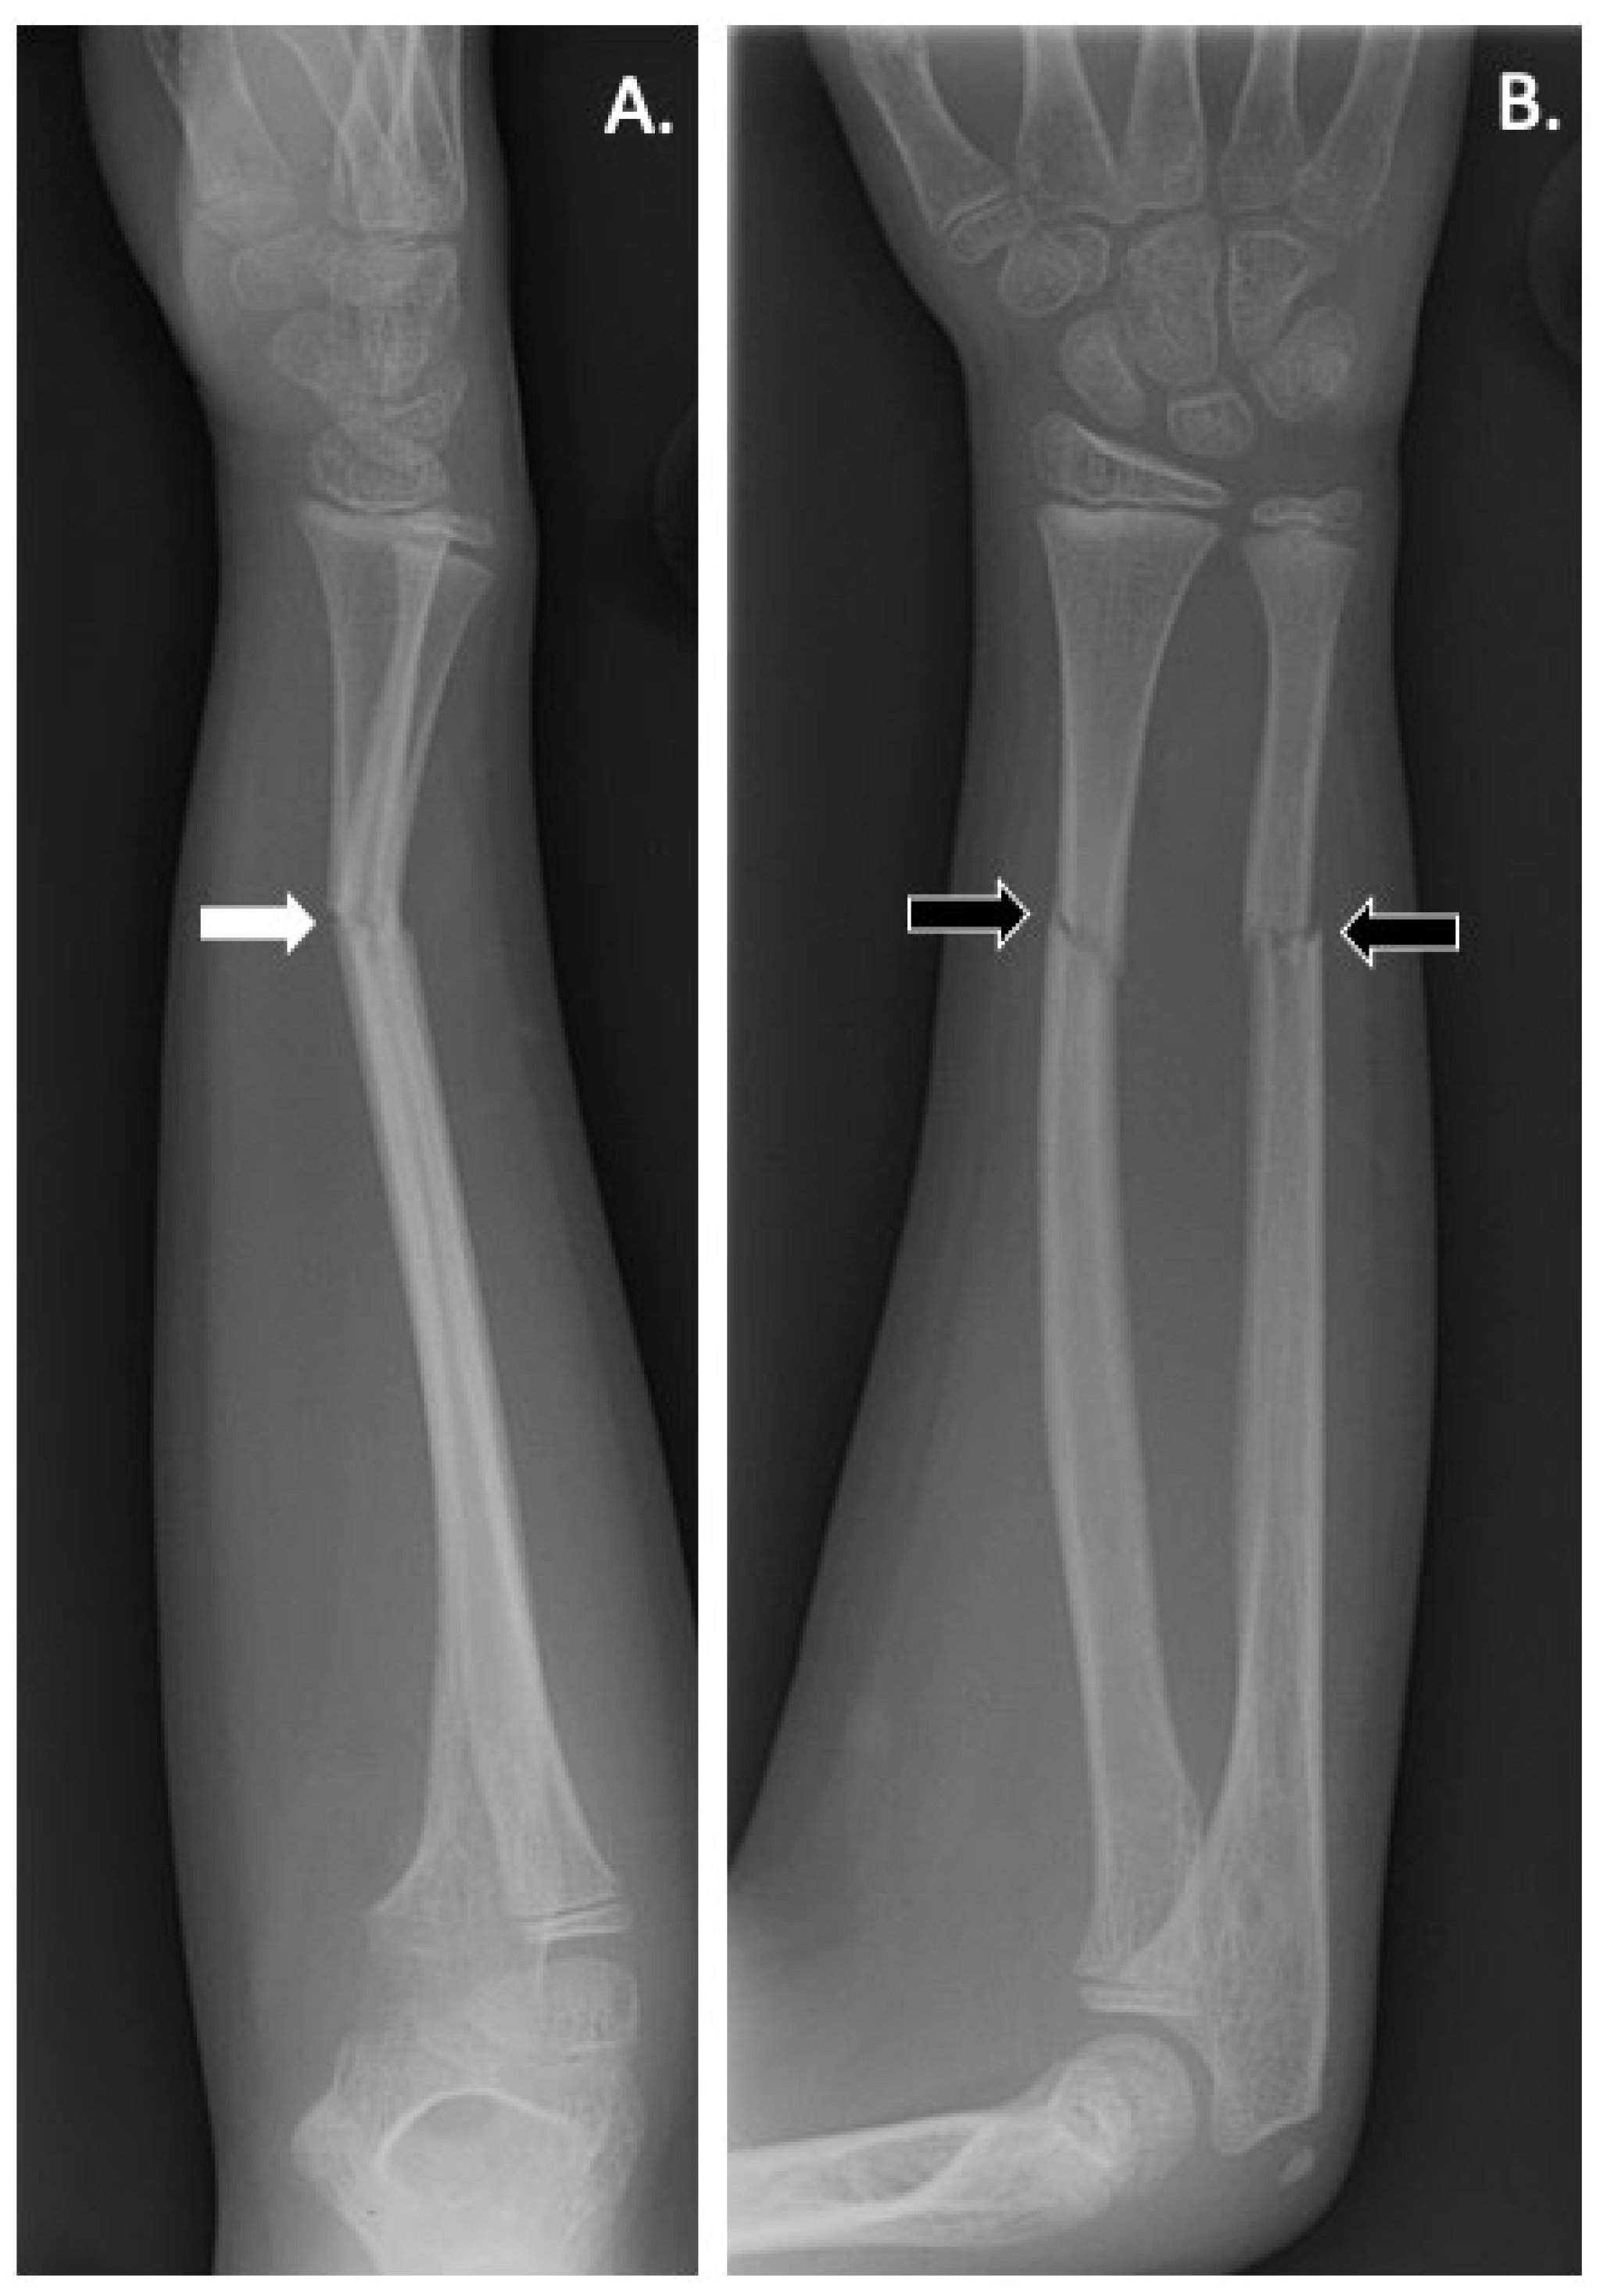

- Littman, J.; Phornphutkul, C.; Saade, C.; Katarincic, J.; Aaron, R. Osteoporosis, Fractures, and Blindness Due to a Missense Mutation in the LRP5 Receptor. Orthop. Res. Rev. 2023, 15, 39–45. [Google Scholar] [CrossRef] [PubMed]

- Korvala, J.; Jüppner, H.; Mäkitie, O.; Sochett, E.; Schnabel, D.; Mora, S.; Bartels, C.F.; Warman, M.L.; Deraska, D.; Cole, W.G.; et al. Mutations in LRP5 cause primary osteoporosis without features of OI by reducing WNT signaling activity. BMC Med. Genet. 2012, 13, 26. [Google Scholar] [CrossRef]